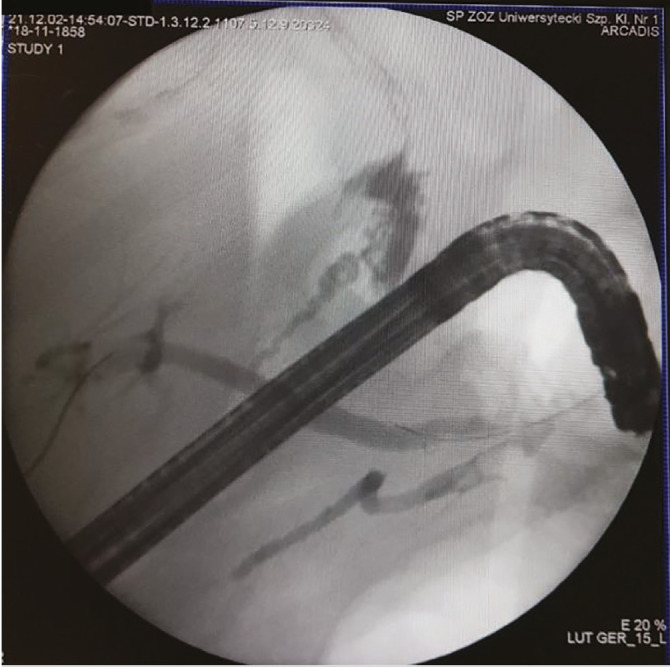

Abstract Image